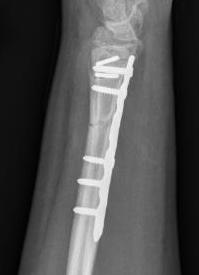

Galeazzi fracture

Galeazzi fracture with DRUJ disruption

Incidence of DRUJ instability after radius ORIF

Rettig et al J Hand Surg Am 2001

- 40 patients with Galeazzi fracture dislocations

- DRUJ instability after radius ORIF

- Type 1: radius fracture < 7.5 cm to articular surface: 55% DRUJ instability

- TYpe II: radius fracture > 7.5 cm to articular surface: 6% DRUJ instability